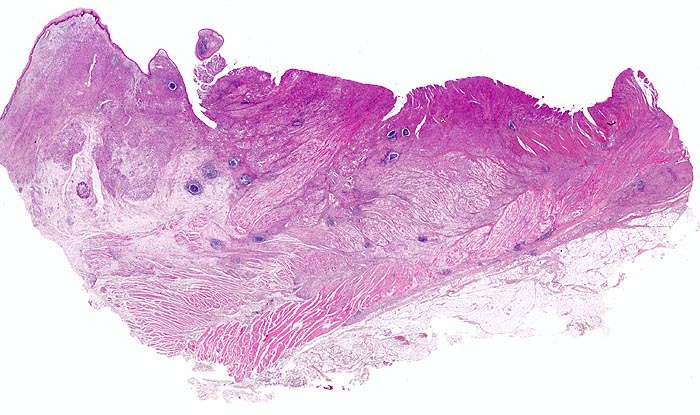

Adenokarzinom des Magens

Oesophagogastrischer Uebergang

Links im Bild der Ösophagus mit intaktem plattenepithelialem $o{ay37517Schleimhautüberzug} Schleimhautüberzug. Rechts der proximale Magen. Das unscharf begrenzte Karzinom breitet sich diffus in der gesamten Magenwand aus. Rechts im Bild sieht man die durch den Tumor aufgesplitterte Muscularis propria. Ausserdem breitet sich der Tumor submukös im Ösophagus aus.

Diffuse Verdickung und Versteifung der Magenwand im Sinne einer Linitis plastica bei intakter Schleimhautoberfläche. Aufhebung des Faltenreliefs.

Die Magenkarzinome können nach Lauren in einen intestinalen und einen diffusen Typ eingeteilt werden. Karzinome vom intestinalen Typ bestehen aus Karzinomdrüsen, welche einen umschriebenen expansiv wachsenden Tumor bilden. Der diffuse Typ besteht aus Tumorzellen, welche keine Drüsen bilden sondern die Magenwand einzeln oder in kleinen Verbänden diffus infiltrieren. Meist handelt es sich dabei um den histologischen Subtyp von Siegelringkarzinomen. Daneben gibt es auch eine Mischform mit Anteilen vom diffusen und vom intestinalen Typ.